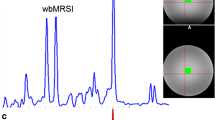

Visual inspection of the data quality was carried out on every spectrum. In nine out of ten subjects, no artifacts were found. However, spurious echoes were observed in one subject. Data from this subject were reacquired. One representative acquisition from each brain region is depicted in Fig. 3. A complete overview of all measured spectra is provided in Fig. 4.

The mean NAA line width within the hippocampus data set was 22.26 Hz for the diff-spectrum, and 22.74 Hz for the off-spectrum. Within PCC the mean line width was 8.68 Hz (diff-spectrum), and 8.88 Hz (off-spectrum). The mean NAA-SNR of the hippocampus data was 35.1 (diff-spectrum) and 43.3 (off-spectrum); while for the PCC, the mean SNR was 168.0 (diff) and 204.0 (off).